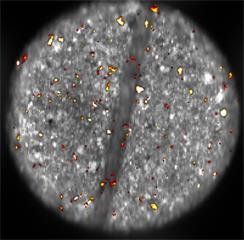

Raman and white light images of MDMA tablet (jpg)